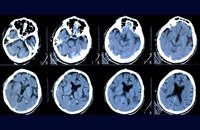

Neurology

Neurosurgery

- Alzheimer’s Disease

- Edrophonium Test

- Electroencephalogram (EEG)

- Electromyography (EMG)

- Epilepsy

- Nerve conduction study (NCV)

- Neuropathy

- Parkinson’s disease

- Stroke

- Acute stroke management for

Cerebrovascular disease - Brain tumour biopsy

- Carotid stenting for Cerebrovascular disease

- Cranial reconstruction and cranioplasty

for Head injury - Craniofacial injury

- Craniotomy for brain tumour

- Craniotomy for haematoma evacuation

- CSF diversion surgery for Hydrocephalus

- Endoscopic neurosurgery for Hydrocephalus

- Intracranial endovascular neurosurgery for

cerebrovascular disease - Keyhole approach for brain surgery

- Microdiscectomy for Spinal disease

- Minimally Invasive Brain Radiosurgery